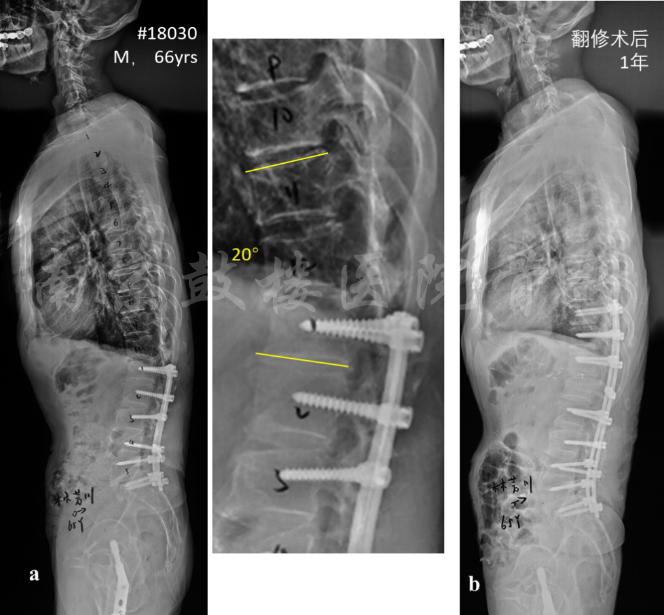

图1 男,66岁,半年前因腰椎管狭窄于当地医院行L1-S1内固定减压融合术,术后2年出现近端交界性后凸,PJA角度20°,伴T12-L1椎管狭窄;于我院行翻修术,去除松动的L1螺钉,行T12-L1 TLIF并将内固定上延至T10,术后1年无PJK(b)